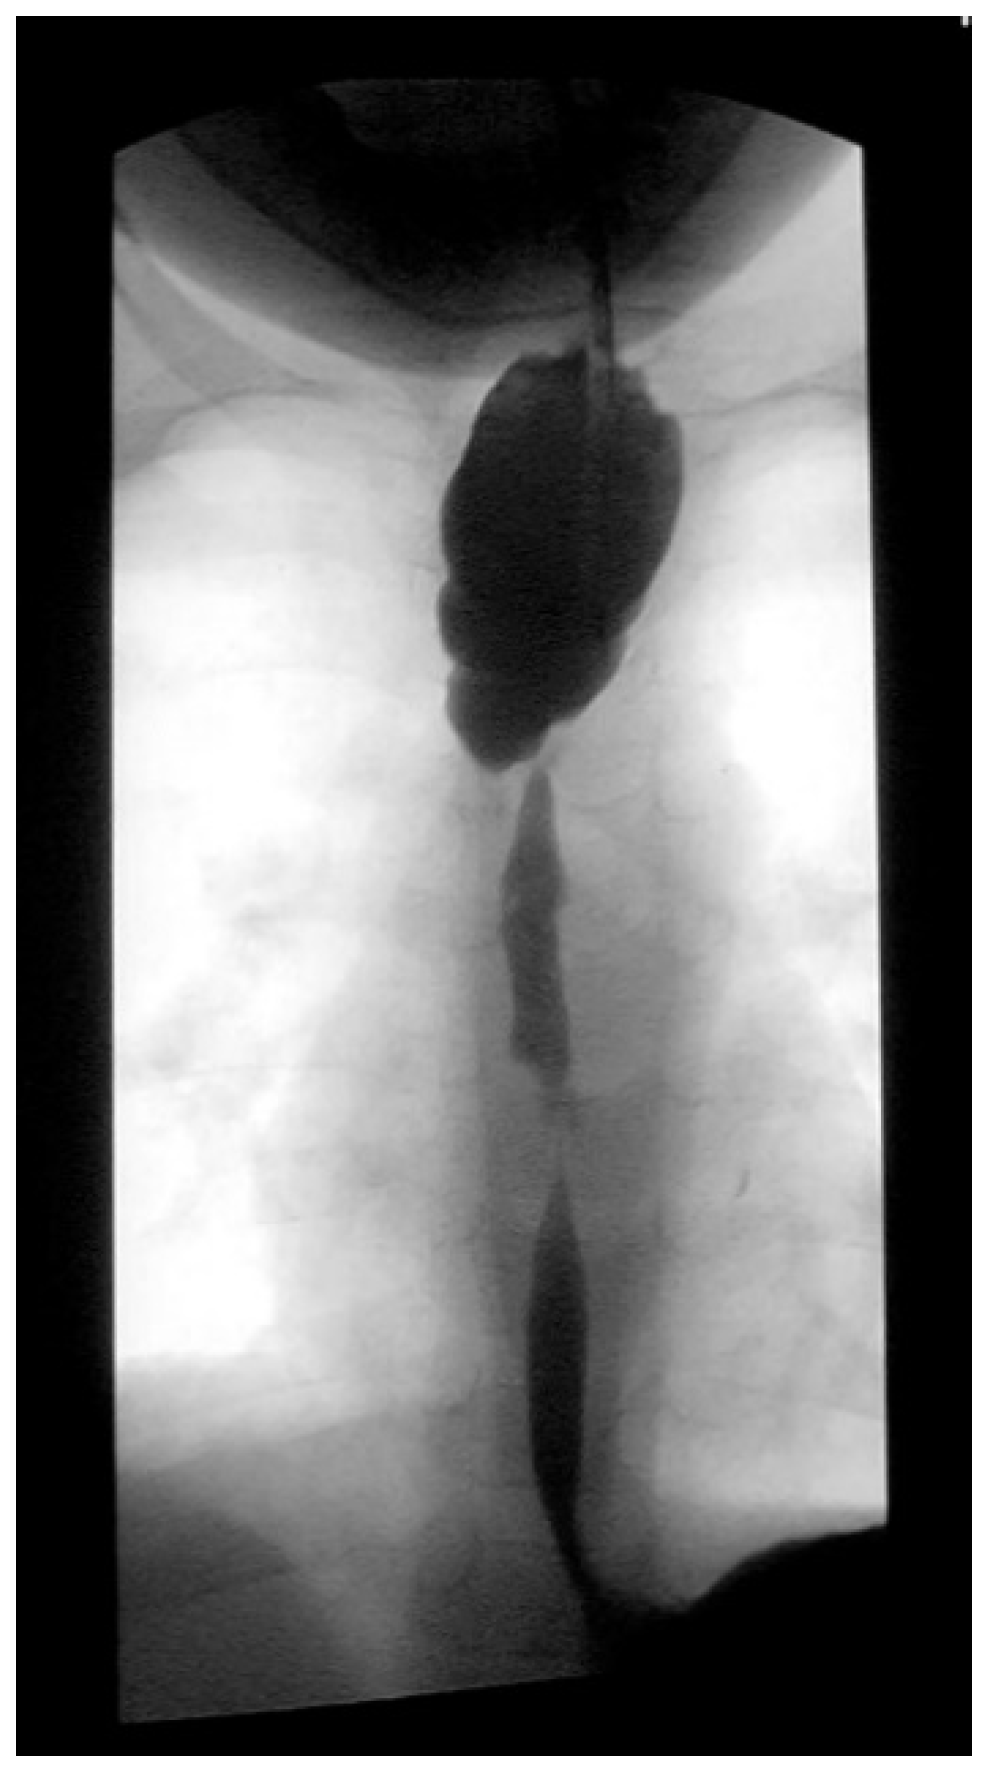

Three weeks before surgery, the children were transferred from Africa to Switzerland for the evaluation of their nutrition status, as they eventually needed to be fed carefully and progressively. A thoracic X-ray and an esophagogram are performed (

Figure 2). Intubation allowed an endoscopic evaluation of the grade of esophageal and pharyngeal stenosis and mobility of the vocal cords (

Figure 3). This evaluation was done with our ear nose and throat (ENT) colleagues, and eventual tracheotomy was discussed for very high stenosis of the larynx without residual damage to the esophagus.